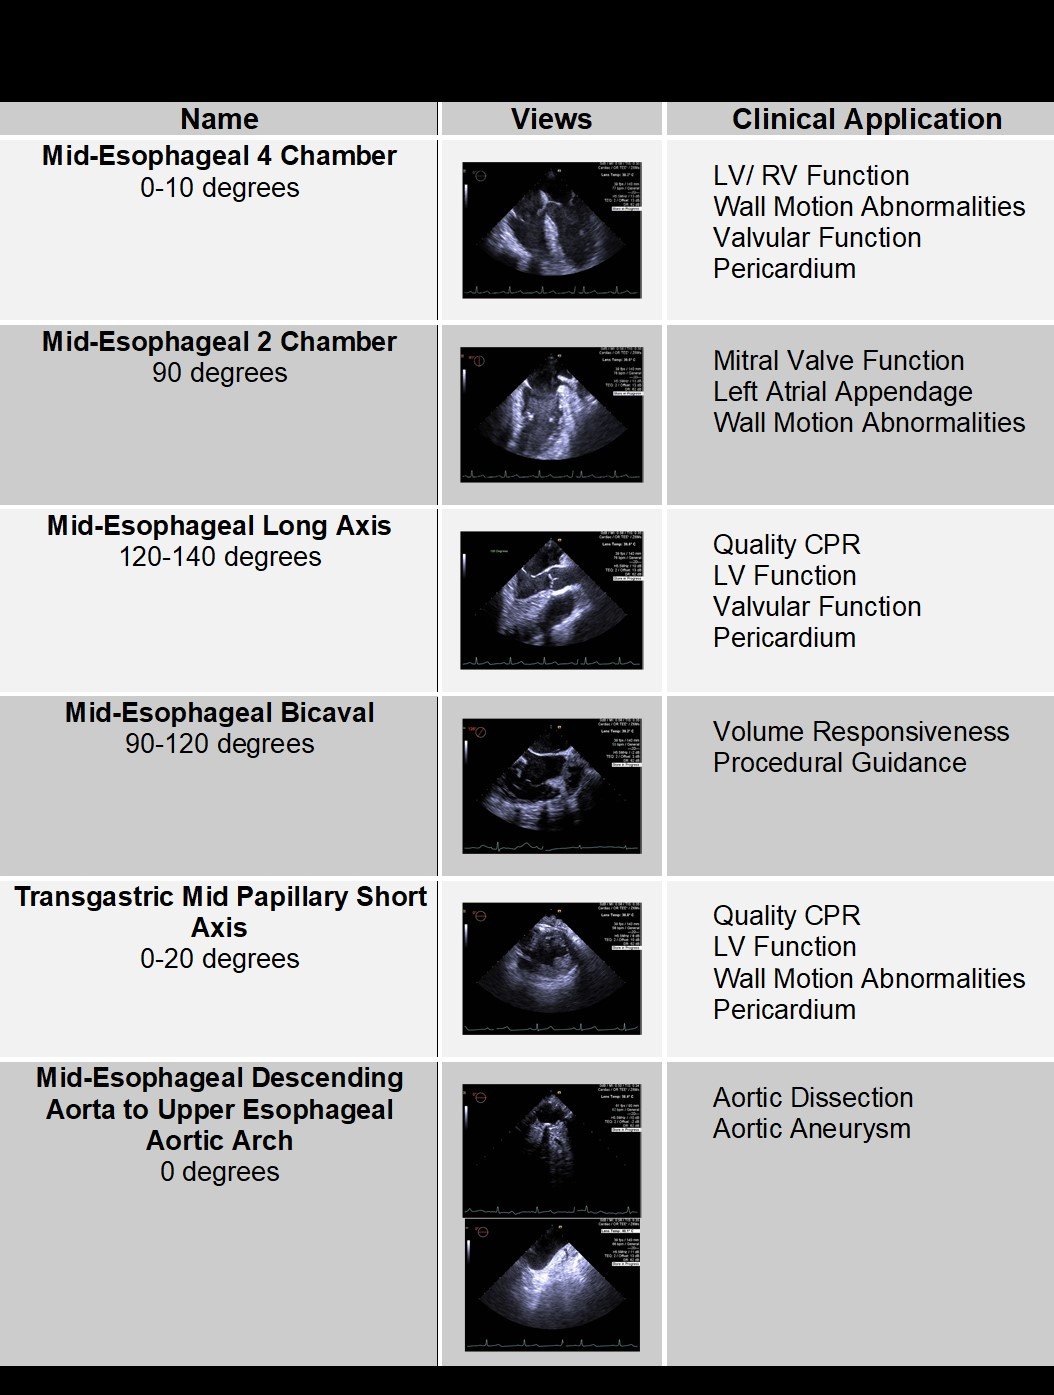

These four views are the:

- Midesophageal 4-Chamber view at 0 degrees

- Midesophageal Long-Axis view at 120 degrees

- Midesophageal Bicaval view at 120 degrees

- Transgastric Mid-Papillary Short-Axis view at 0 degrees

Quick Six

In addition to the published views for TEE in cardiac arrest, we propose two supplemental views that provide additional information in both the peri-arrest and cardiac arrest patient and can be used in settings beyond the ED.7 These include the Mid Esophageal 2-Chamber View at 90 degrees and the Descending Aorta and Aortic Arch View at 0 degrees.

How To Obtain The Supplemental Views

These two additional views are easily obtained. The first view is the Midesophageal 2 chamber view which is obtained by simply increasing the omniplane to 90 degrees from the midesophageal 4 chamber view at 0 degrees. This will afford the examiner views of the anterior and inferior walls of the left ventricle as well as the mitral valve. This is clinically useful in the setting of possible acute myocardial infarction and also provides a great view of the mitral valve allowing one to assess for valvular dysfunction or vegetation. The second view can be obtained from the Transgastric Mid Papillary Short Axis view by returning the omniplane to 0 degrees and rotating the probe to patient’s left. Slowly withdraw the probe until the descending aorta is seen. One then continues withdrawing the probe while keeping the aorta in view, until the aortic arch is reached in the upper esophagus. To get a more complete view of the aortic arch one must rotate the probe slightly towards the patient’s right. This extra view is simple to acquire and adds a great deal of information about the aorta, assessing for dissection or aneurysm, while one is removing the probe.